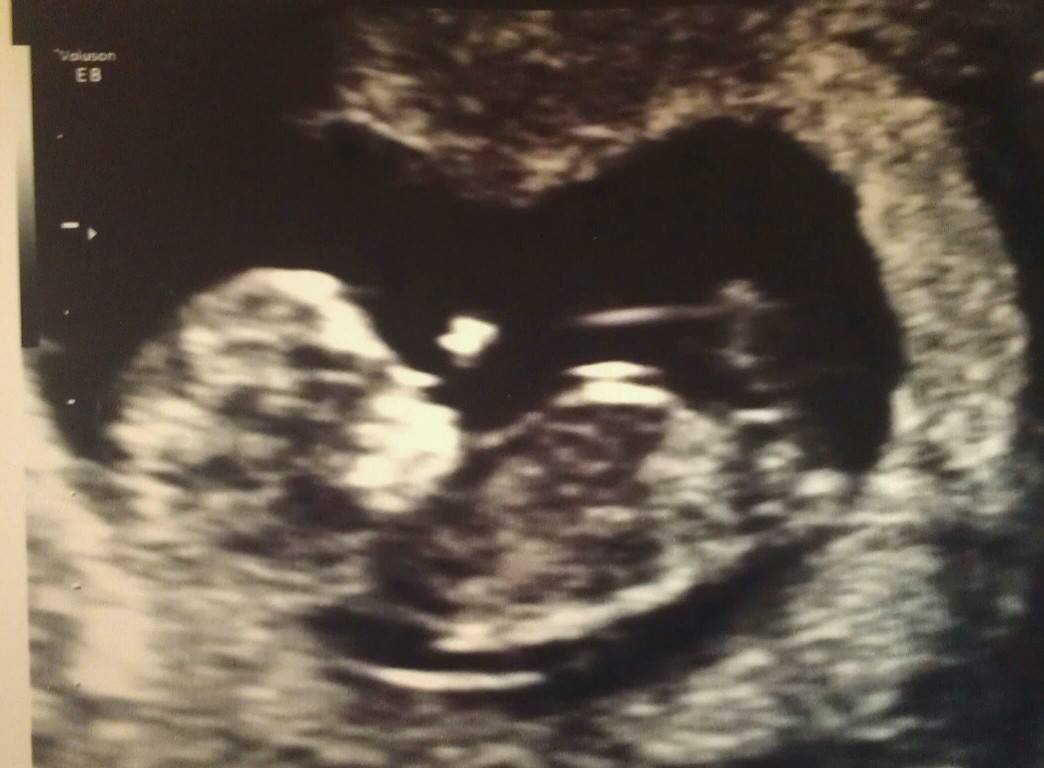

Hey Everyone!! I will have a confirmed blood test result next week and I will post back w/ the confirmed gender but I am dying to know y'alls opinions and input as I have a feeling it is a boy but have no idea what to look for!! Any input is greatly appreciated!!! THANK YOU :-D

Attachment 12682